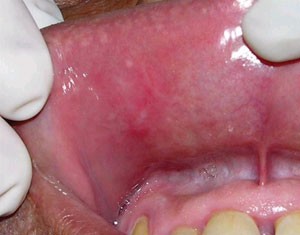

Sir, promoted by the paper by Gilvetti et al.,1 we would like to report a further case. A 50-year-old male was referred to our oral medicine clinic complaining of a painful ulcer on his upper lip. The patient reported a previous history of long-standing recurrent aphthous stomatitis (RAS) that had been treated elsewhere without relief of the symptoms, which had recurred nine days previously. In an attempt to alleviate the local pain he placed cotton wool soaked in formalin (37%) on his upper lip mucosa. Oral examination revealed a white pseudomembrane covering an extensive ulcer (2.5 × 2.5 cm diameter) with irregular borders. The lesion was associated with intense pain during mouth opening and lip palpation (Fig. 1) and was diagnosed as traumatic chemically induced oral ulceration. The patient was informed about the risks of self-treatment without professional advice and received instructions to maintain excellent oral hygiene. The mucosa injury completely resolved spontaneously after 21 days of clinical follow-up (Fig. 2).